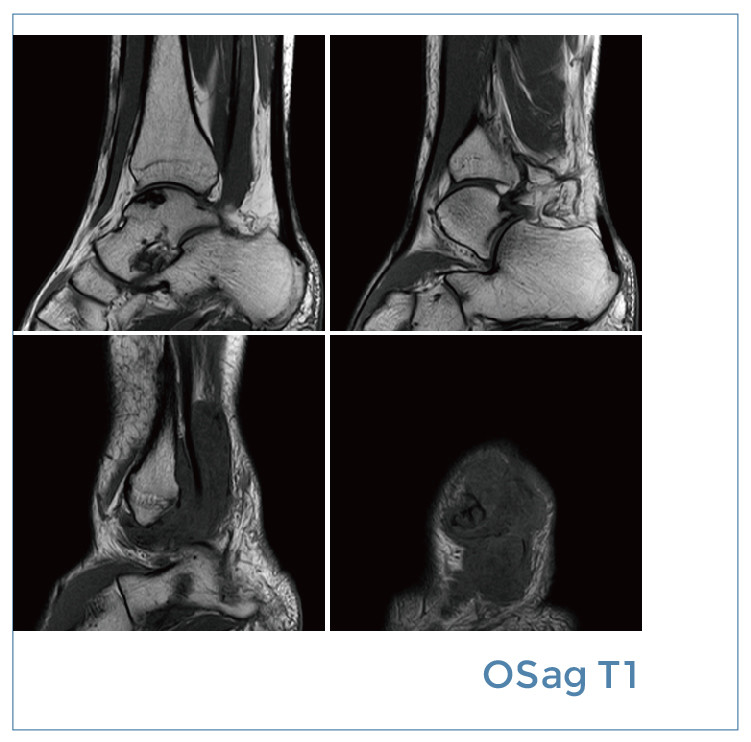

【朗润影像档案】磁共振影像病例分享(编号20191206)